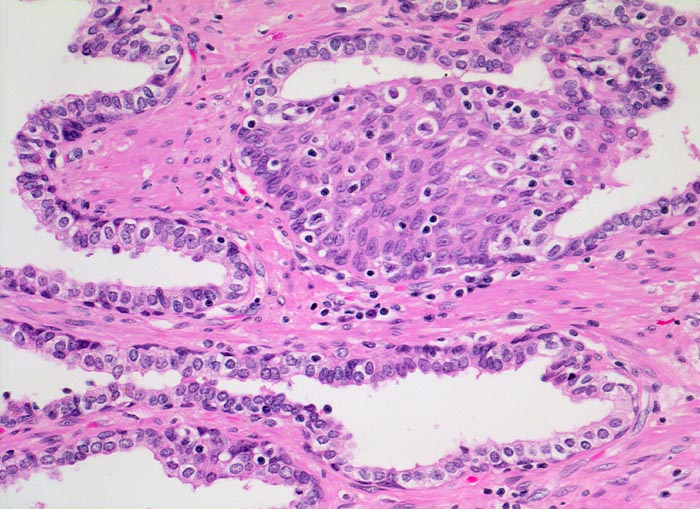

• Normale Prostatadrüsen mit grossen Lumina angeordnet in Läppchen. Das Epithel bildet Falten und besteht aus einer inneren hochprismatischen sekretorischen Zellschicht und einer äusseren Schicht flacher Myoepithelien.

• Herde kleiner Karzinomdrüsen ohne Basalzellschicht.

• Karzinomzellen mit stark erhöhter Kern-Zytoplasmarelation und hyperchromatischen Zellkernen mit grossen eosinophilen Nukleolen.